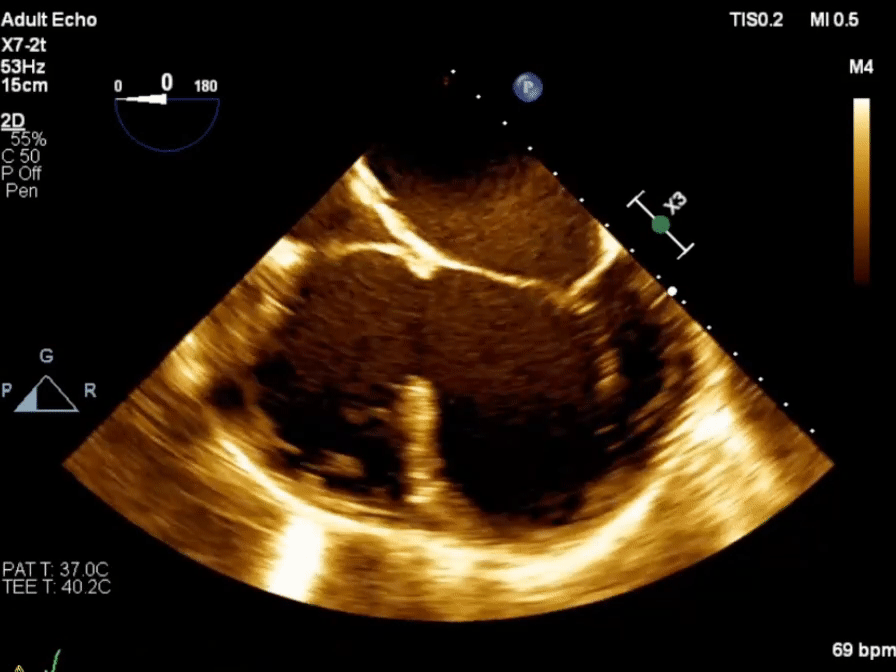

Echo in VSD

-1754871370645.webp)

-

Membranous VSD

Inlet VSD